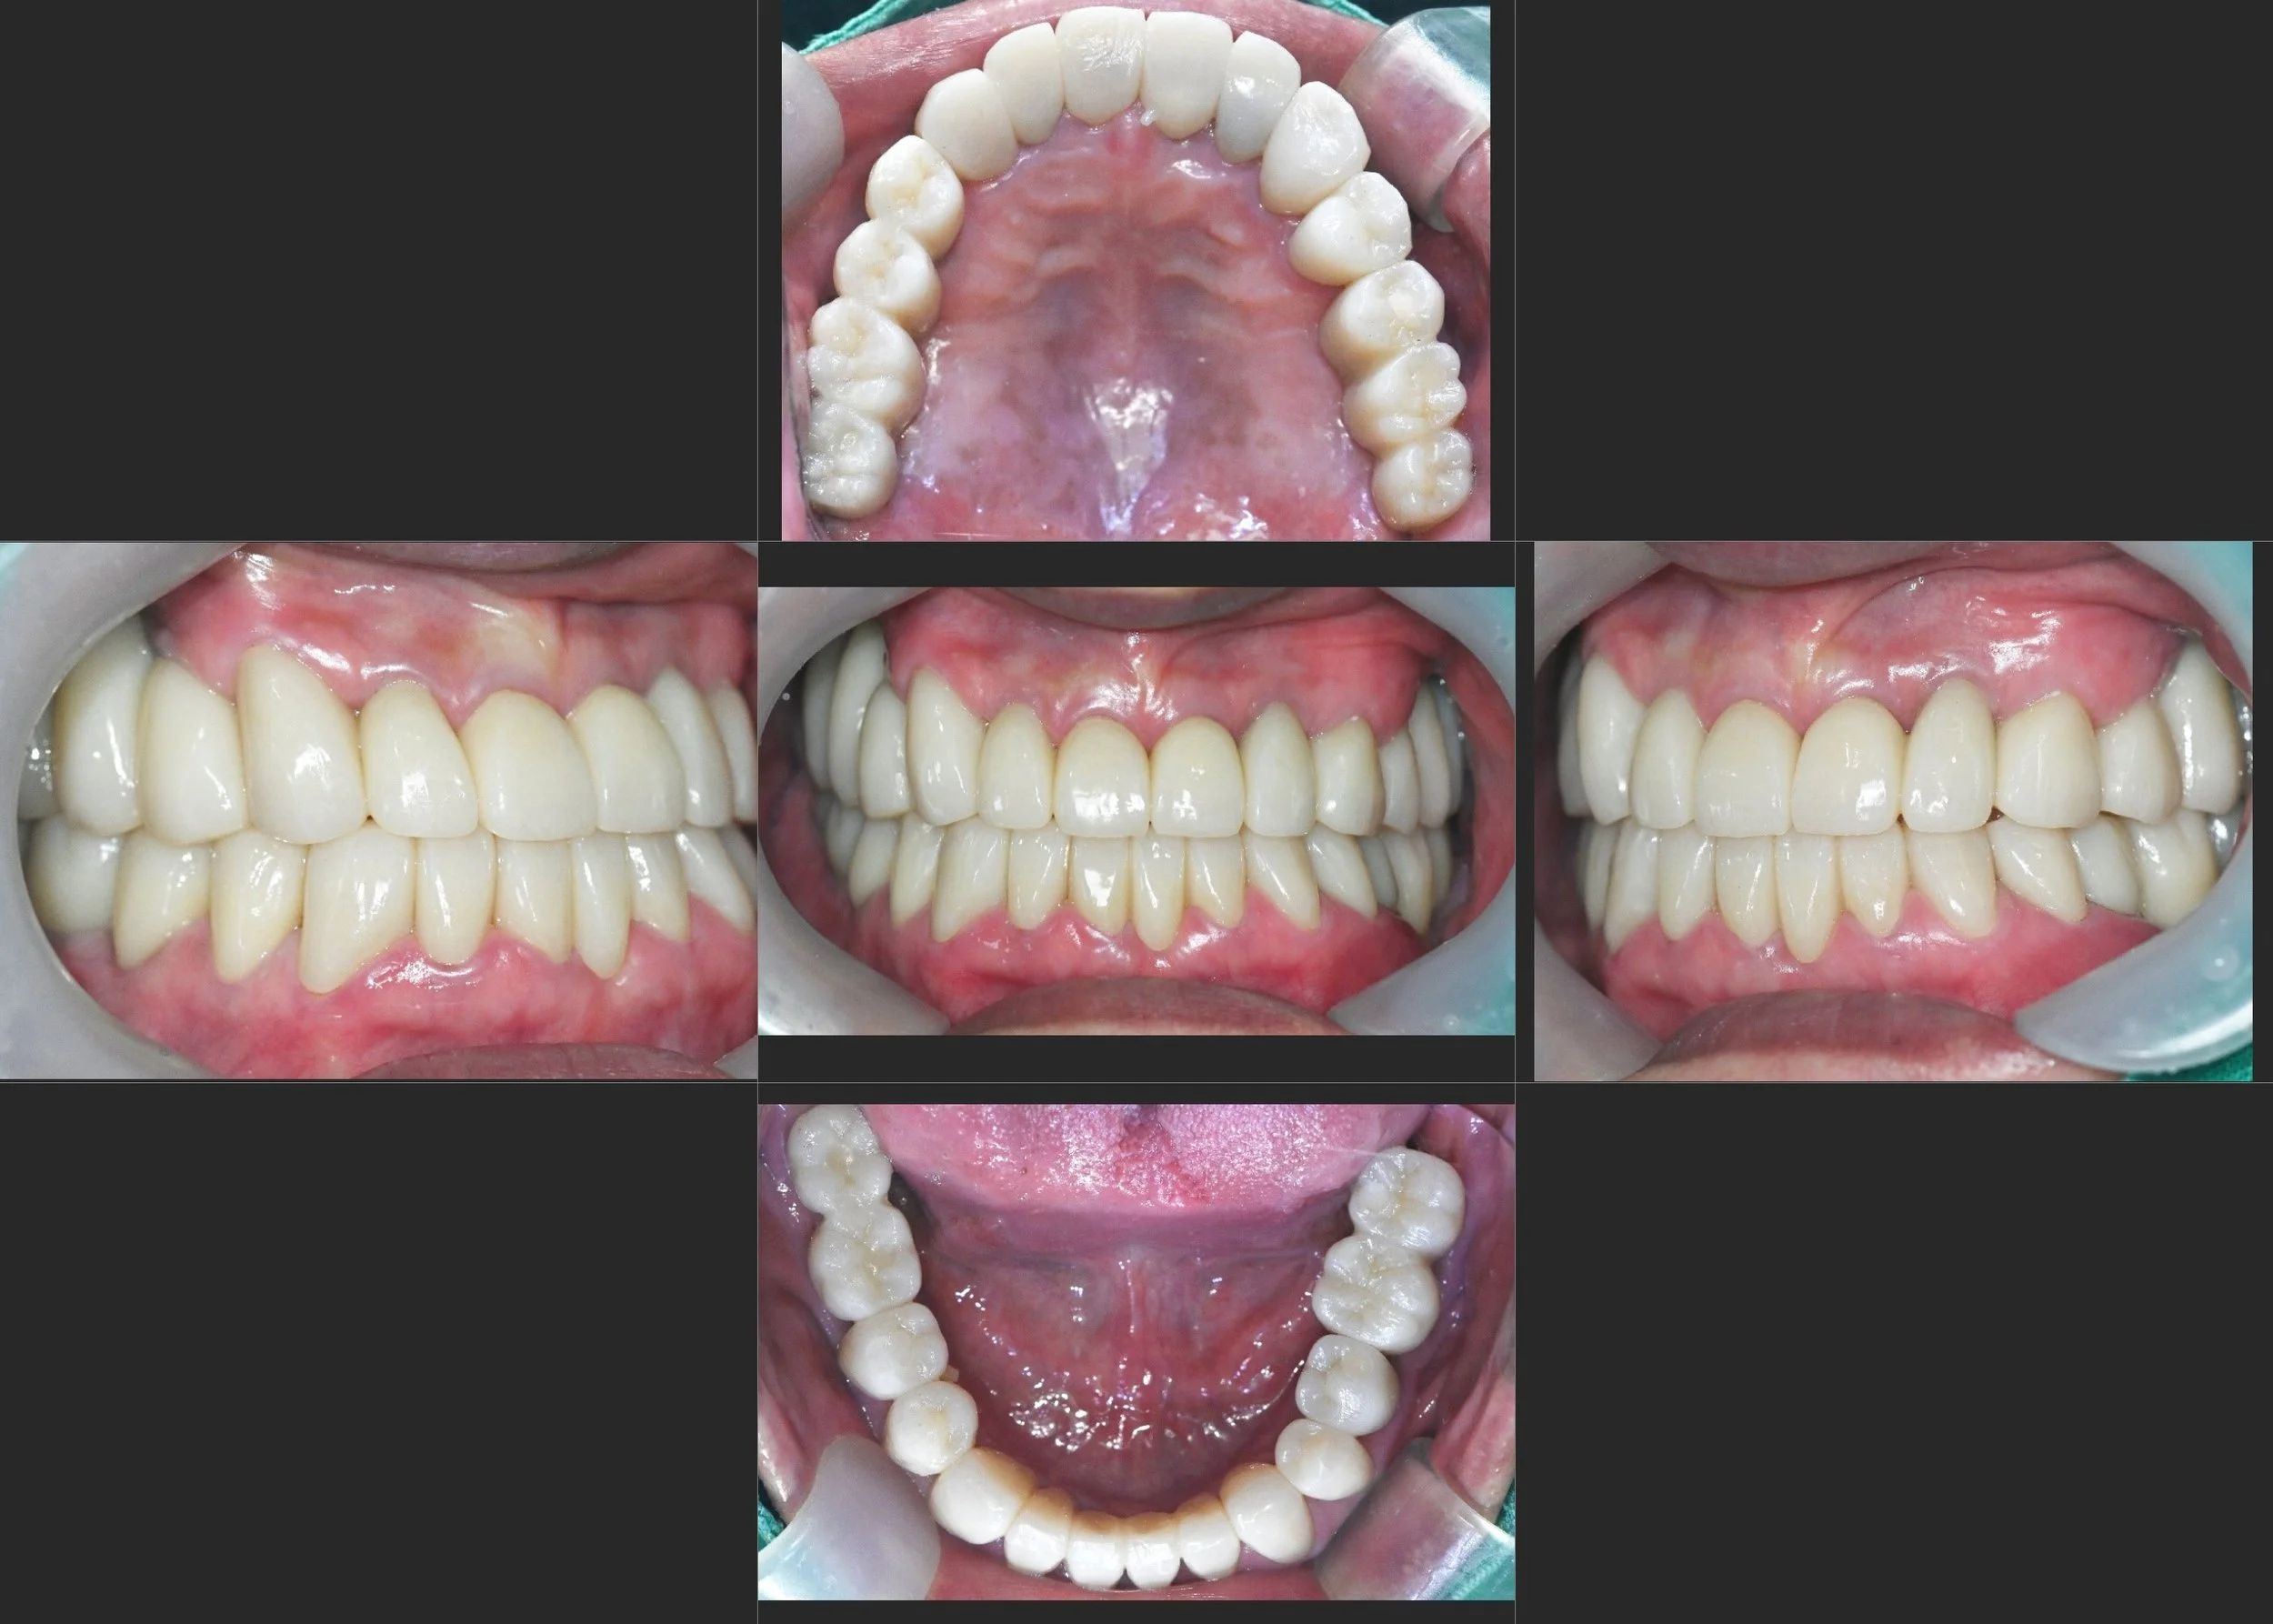

INTRA ORAL - BEFORE

• Severe Skeletal Malocclusion: Pronounced prognathic tendency with unstable occlusal stops.

• Functional & Skeletal Asymmetry: Significant mandibular deviation, visibly affecting facial symmetry.

• Iatrogenic Implant Failure: Existing implants located in positions that made functional restoration impossible, acting as destructive occlusal interferences.